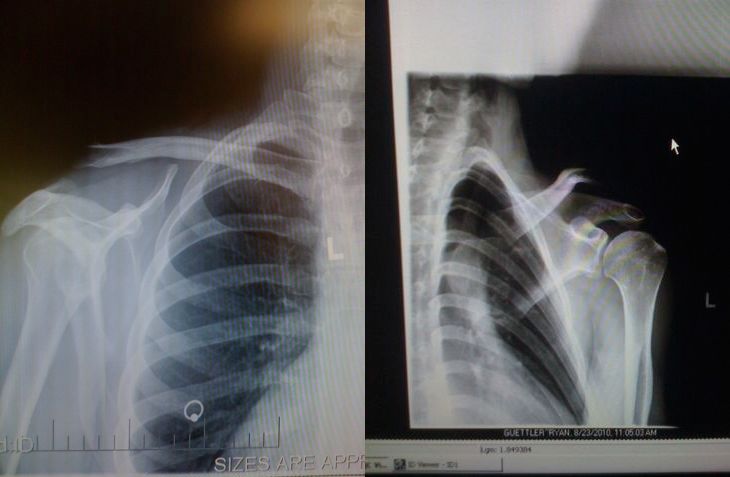

3 weeks ago was my first shoulder surgery and everything went very well. Yesterday I came out of the sling but on the same day went straight into sugery on my left shoulder. My left shoulder is the one with the 3rd degree separation so they had to put a plate in my shoulder, this made the surgery 8-1/2 hours long. Being out for that long I had a crazy dream, I was dreaming that I was riding and it felt so real that after my surgery was done I thought that I had crashed and was in the hospital for the crash. Also being out for that long when I woke up, my leg was asleep and I couldn’t move my arm. For a split second I thought I was paralysed. It’s pretty crazy going through this right now. I havent had a serious crash in 6 years or so.